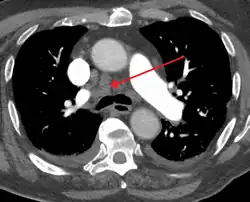

| Widened mediastinum | |

| Other names | Mediastinal widening |

![]() | |

| Widened mediastinum in a patient with achalasia | |

Widened mediastinum/mediastinal widening is where the mediastinum has a width greater than 6 cm on an upright PA chest X-ray or 8 cm on supine AP chest film.[11]

A widened mediastinum can be indicative of several pathologies:[12][13]

- aortic aneurysm[14]

- aortic dissection[15]

- aortic unfolding

- aortic rupture

- hilar lymphadenopathy

- anthrax inhalation - a widened mediastinum was found in 7 of the first 10 victims infected by anthrax (Bacillus anthracis) in 2001.[16]

- esophageal rupture - presents usually with pneumomediastinum and pleural effusion. It is diagnosed with water-soluble swallowed contrast.

- mediastinal mass

- mediastinitis

- cardiac tamponade[17]

- pericardial effusion

- thoracic vertebrae fractures in trauma patients.